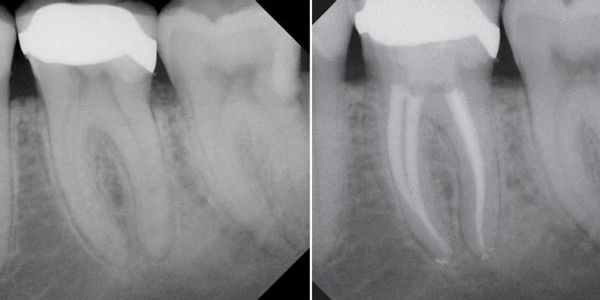

Le traitement de canal est nécessaire quand la pulpe de la dent est infectée suite à une carie importante, des fissures à l’émail ou un traumatisme. Si la pulpe enflammée, infectée ou nécrosée, cela peut causer des douleurs ou conduire à un abcès. Ce traitement consiste à enlever la pulpe infectée des canaux. La dent est ensuite reconstituée soit avec une obturation coronaire ou une couronne.

Le traitement d’endodontie mécanisé présente plusieurs avantages par rapport au traitement qui utilisait des limes manuelles:

Il est plus rapide et plus confortable pour le patient

Permet d’offrir un traitement de qualité supérieure